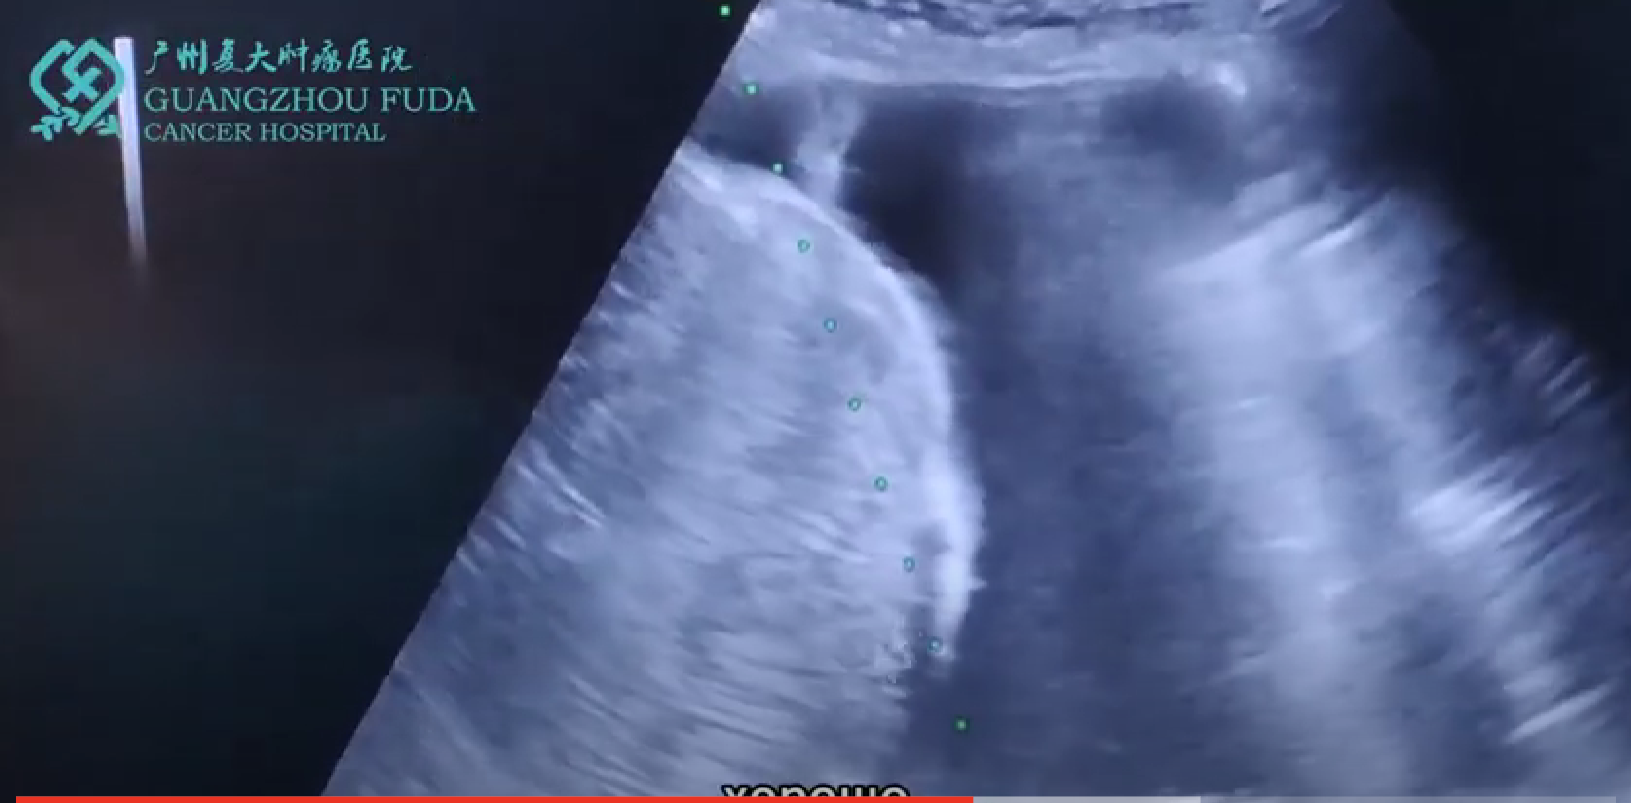

Аргоно-гелиевая Криоабляция проводится через интраоперационные, эндоскопические или чрескожные пути. Чрескожная криохирургия используется чаще всего. При применении УЗИ и КТ введут криозонд в опухоль, пустят аргон для снижения температуры внутри опухоли, затем вместо аргона пустят гелий для повышения температуры. В этом процессе формируется ледяной шарик. Эта процедура повторяется минимально 2 раза.

Большинство пациентов подвергаются общей анестезии во время криоабляции. Во время лечения прокола обычно проводится под контролем УЗИ или КТ, чтобы контролировать весь процесс прокола в режиме реального времени. Методы хирургической прокола включают чрескожный прокол, прокол во время операции и эндоскопический прокол. Под руководством УЗИ или КТ нож газа аргона точно прокалывается в место опухоли, а затем запускается газ аргона. Газ аргона быстро расширяется на кончике ножа, создавая охлаждающий эффект, и больная ткань охлаждается до минус 140 ° C ~ 170 ° C в течение 15 секунд. После того, как этот процесс длится 15-20 минут, выключите газ аргона и запустите газ гелий. Гелий быстро расширяется на кончике ножа и быстро нагревает больную ткань в сверхнизком температурном состоянии, что может повысить температуру больной ткани от минус 140 ° С до минус 20° С ~ 40 ℃ для быстрой гипертермии. После 3-5 минут снова охладите и нагрейте, по крайней мере, 2 цикла.

Замораживание продолжается до тех пор, пока ледяной шарик не покроет всю опухоль и окружающие нормальные ткани 5-10 мм. Что касается опухолей больщего размера, то часто используют несколько криозондов для замораживания. В зависимости от реальной ситуации криохирургия иногда проводится не менее 2–3 раза. Этот тип температурной терапии особенно тщательно разрушает пораженные ткани. Скорость, время и температура охлаждения и нагрева, размер и форма разрушенной области могут контролироваться в режиме реального времени с помощью УЗИ или КТ и т. д., А также точно настраиваться и контролироваться компьютером. Что еще более важно, поскольку охлаждение или нагревание аргон-гелиевого ножа ограничено кончиком ножа, это не вызовет горячего и холодного повреждения ткани в месте прокола.

Криоабляцией опухоль фиброзного капсулы печени...